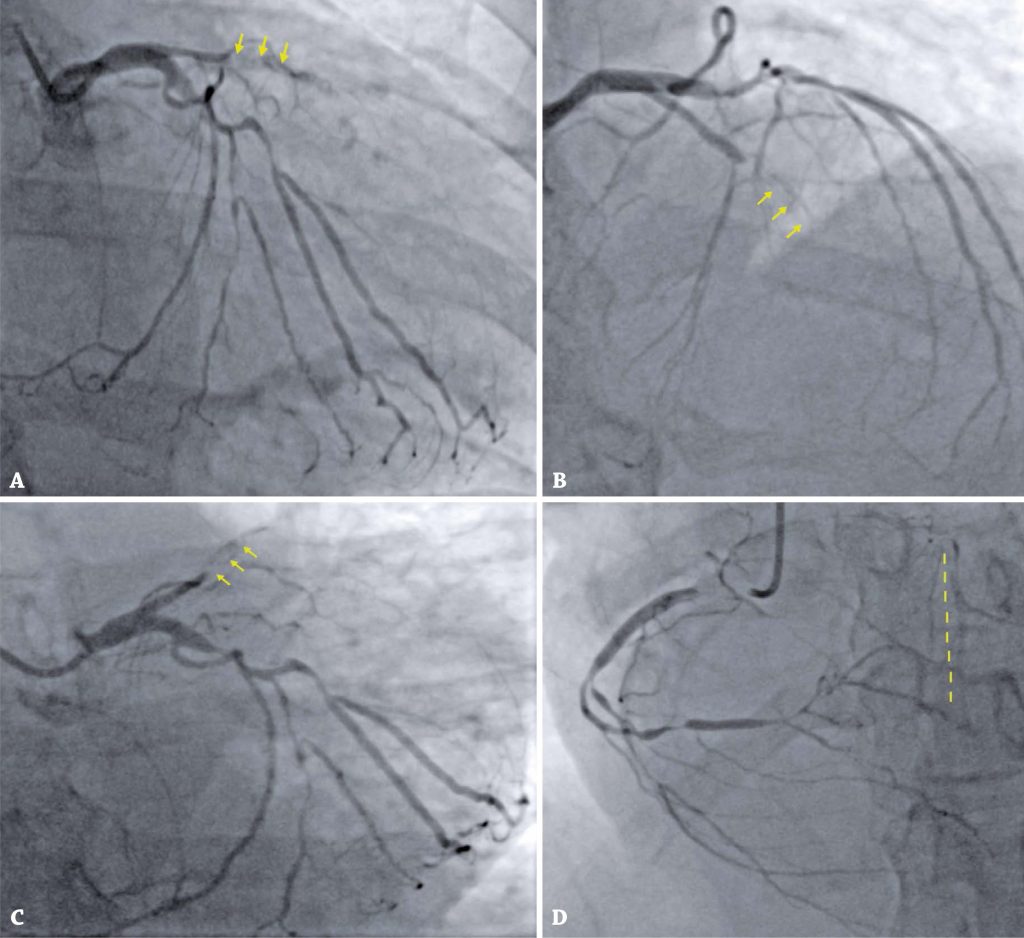

COVID-19 induced type 2 myocardial infarction in a patient with unknown severe coronary artery disease

Myocardial infarction is well described in the COVID-19 pandemic and specific protocols should be developed in the context of acute management of this condition. The relation between myocardial injury and death is well established in the literature and is associated with an increased need for invasive ventilation and other complications. Type 2 myocardial infarction and new onset of heart failure have been diagnosed more frequently in the setting of COVID-19. Particular emphasis should be placed on timing for invasive procedures, such as coronary interventions and coronary artery bypass graft in a SARS-CoV2 positive. We describe a case of a COVID-19 patient with no past cardiac history, who was admitted with symptoms of heart failure and markers of myocardial injury, suggestive of type 2 myocardial infarction.